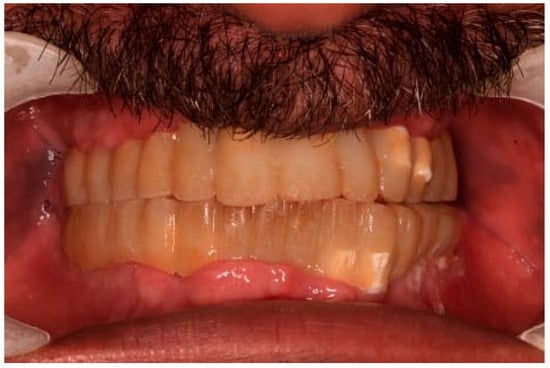

Each telescopic crown was sandblasted on the internal surfaces, then placed in an ultrasonic bath and treated with the manufacturer-specified “Bredent” solution. A resin cement was utilized to bond each telescopic crown to its respective zirconia abutment. The arches were scanned once again and sent to the lab for the fabrication of segmented zirconia bridges, which were subsequently provisionalized with PEEK crowns (Figure 11, Figure 12 and Figure 13).

Figure 14. The final prostheses.